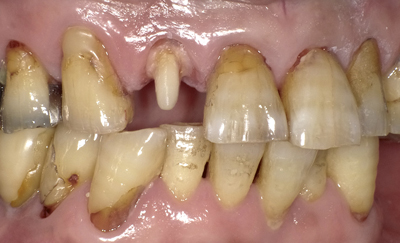

奈良より60代の男性。主訴は「前歯がグラグラしていて外れそうなので入れ歯が使えない。3年前に治療してもらった先生に訴えると『上の前歯を全部抜いて、総入れ歯にした方がいいですね』と言われた。恐くなって友達の紹介でここに来た。少しでも残したい。歯の無い所は、部分入れ歯でお願いしたいのですが…」でした。

上記写真は、そいの合ってない6連結の被せ物を前歯から取り除いたところです。

精査の結果、6本中→5本を抜かずに残すことに(1本のみ抜歯)なりました。 続きを読む